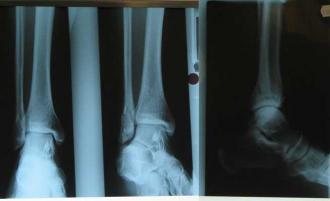

Yeah, yeah I know. Who breaks their leg playing badminton? You can see a spiral fracture of my fibula down near my ankle.